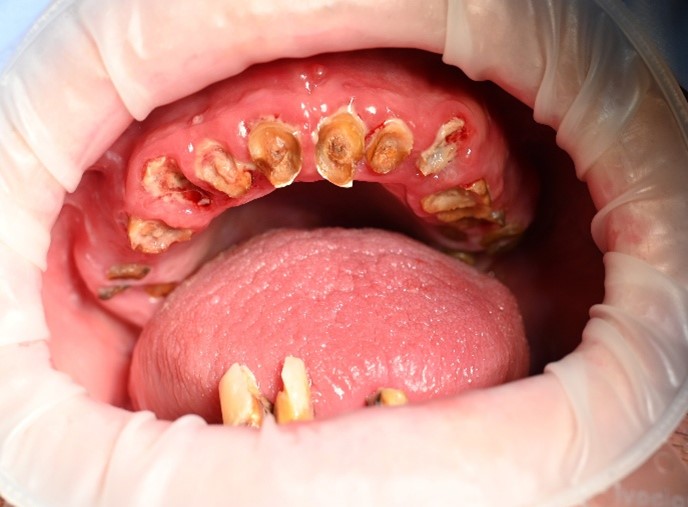

We completed a full clinical examination and took detailed records, including:

• clinical photographs

• intraoral photos

• OPG x-ray

• CBCT scan

• digital implant planning records

These records helped us carefully assess bone levels, gum health, and implant positions.

xAlthough the patient had moderate bone loss in some areas and signs of old chronic abscesses, his overall bone quality was still suitable for implants. There was no active pus or severe infection at the time of treatment.

We also discussed smile design and tooth shade with the patient so that the final result would feel natural and suit his face.